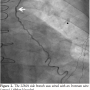

Case Report. A 60-year-old man with a history of diabetes mellitus, hypertension, and paroxysmal atrial fibrillation, presented with angina in spite of intensive antianginal medical therapy. A stress test demonstrated anterior ischemia. He had undergone CABG 7 years prior to presentation with implantation of a LIMA to the left anterior descending artery (LAD) and 2 saphenous vein grafts (SVG) to the posterior descending artery and the second obtuse marginal artery. Although angina improved after CABG, he continued to have exertional chest pain that subsequently worsened. Coronary angiography revealed that all bypass grafts were patent. The LIMA to LAD had a large side branch (Figure 1). In view of the severity of the patient’s symptoms and the lack of other possible culprit lesions, percutaneous occlusion of the LIMA side branch was planned.

Left radial access was obtained with a 6 Fr sheath. The LIMA was wired with an Ironman wire (Abbott Vascular; Figure 2) and a Proxis catheter (St. Jude Medical) was inserted into the LIMA side branch (Figure 3). We attempted to deliver a 3 mm Amplatzer vascular plug (AGA Medical) through the Proxis catheter in the LIMA side branch, however significant resistance was encountered during delivery attempts. The device was partially deployed but in suboptimal location due to movement of the catheter during delivery. The vascular plug was recaptured and removed. LIMA angiography demonstrated side-branch occlusion. The LIMA side branch remained occluded after 15 minutes of observation. The patient had an uneventful recovery and has had no recurrent angina during 3 months of follow-up.